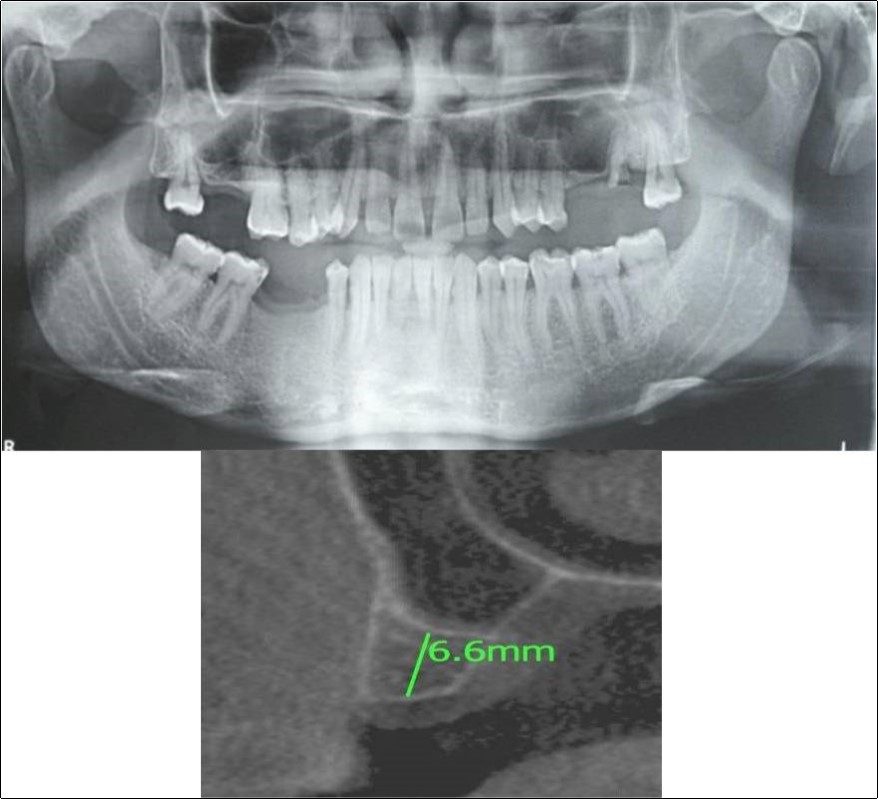

Figure 11.(a,b) Pre-treatment OPG and cross section of CBCT showing residual alveolar bone height for Case No.3

Figure 12.(a,b) Post-treatment OPG and cross section of CBCT showing residual alveolar bone height for Case No.3;

Clinical and Radiological Assessment:

1.Partially edentulous maxillary arch with missing 16;

2.Increased pneumatisation of right maxillary sinus;

3.Height of available bone- 5.3mm;

4.Transverse thickness of available bone (CBCT evaluation)- 10.2mm;

5.Inter-ridge space adequate to place implant (10mm).

Treatment:

Patient underwent the procedure of indirect sinus elevation using sinus osteotomes in relation to 16 region. Calcium phosphosilicate putty was dispensed as the graft material through the crestal osteotomy site to maintain the elevated sinus membrane followed by placement of a dental implant measuring 5 x 10mm under local anaesthesia and strict aseptic protocols. The implant was allowed to osseo-integrate for a period of six months during which the patient was followed-up periodically and was assessed for peri-implantitis, crestal bone loss and mobility. At the end of 6 months, a repeat CBCT scan was advised to evaluate the increase in bone height. (Figure 11a,b, pre-treatment; Figure 12a,b, post-treatment)